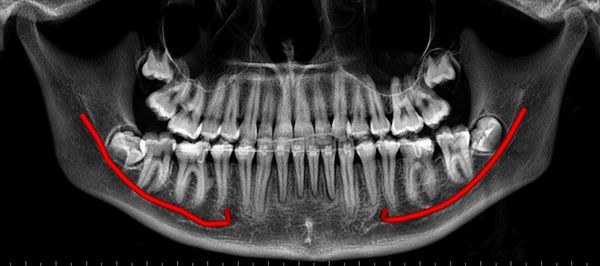

CBCT derived Grey-scale Panoramic view (OPG) of the Jaws

CBCT derived Panoramic view (OPG) of the Jaws

CBCT derived Osseous Panoramic view (OPG) of the Jaws